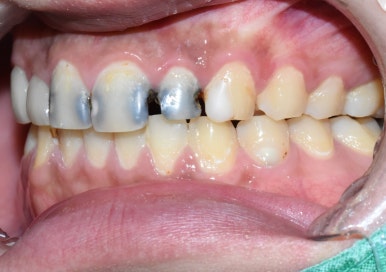

대문이 2개는 신경치료하고 앞니 크라운 2개 하셔서 2개는 크라운까지 완성된 상태구요.

사진상 오른쪽(환자분 기준으로는 왼쪽) 두번째 치아는 아직 크라운을 못하시고

신경치료 하고 사회생활은 하셔야하니 현재 레진으로 만들어놓은 임시 상태인데

환자분이 시간이 없이 너무 바쁘셔서 일단 다음번에 크라운 작업 시작하기로 한 상태입니다.

어쨌든 사회생활은 하실만큼 만들어놓은 상태죠.

처음과 비교하면 보기에도 훨씬 깨끗하고 좋아졌습니다.

앞니 크라운 2개와 옆치아 1개는 임시레진상태